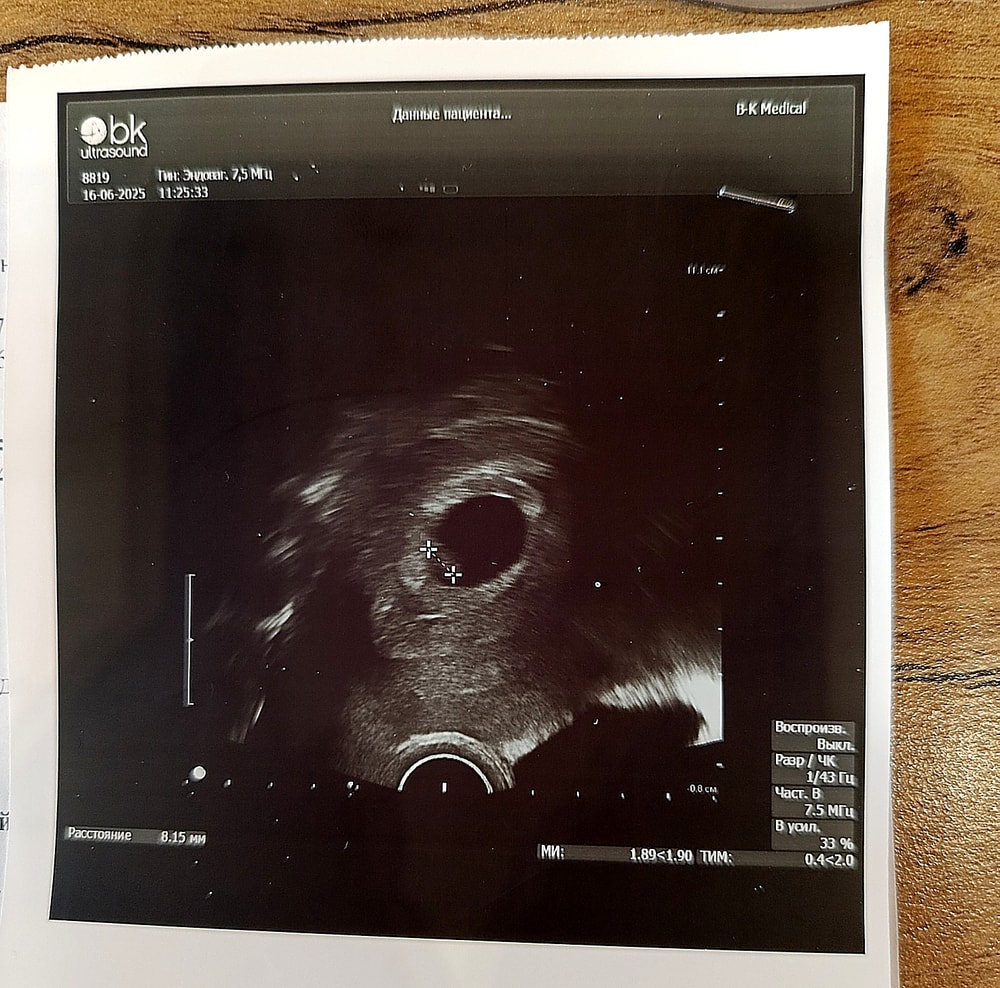

Плодное яйцо 22 мм, ктр 7 мм, сб+